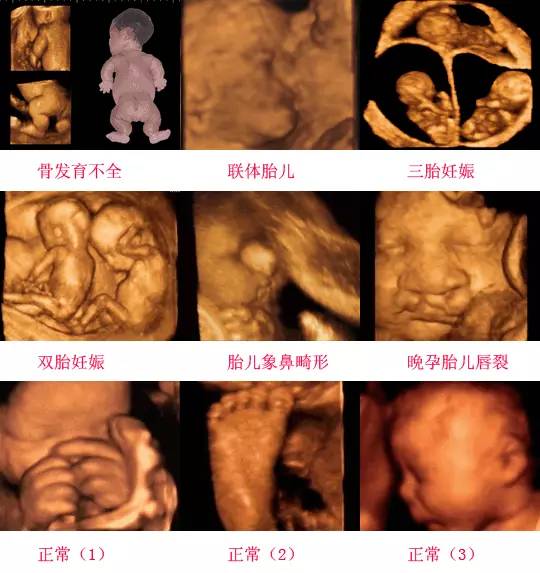

四維彩超是一種先進的醫學影像技術,通過實時觀察胎兒在母體內的活動情況,為醫生提供了豐富的診斷信息,在四維彩超下,我們可以清晰地觀察到胎兒的蛋蛋(睪丸)的形態、位置和大小等特征,胎兒蛋蛋是男性生殖系統的重要組成部分,對于胎兒的生長發育具有重要意義。

四維彩超下胎兒蛋蛋的樣子

在四維彩超下,胎兒蛋蛋呈現出特定的形態和外觀,通常情況下,胎兒蛋蛋呈現出圓形或橢圓形,表面光滑,內部回聲均勻,隨著胎兒的發育,蛋蛋會逐漸增大,并呈現出明顯的性別特征,醫生可以通過四維彩超技術,對胎兒蛋蛋的大小、形態和位置進行評估,以判斷胎兒生殖系統的健康狀況。

胎兒蛋蛋的發育是一個復雜的過程,受到多種因素的影響,在胎兒發育的早期階段,蛋蛋位于腹腔內,隨著胎兒的生長發育,蛋蛋逐漸下降至陰囊,這個過程受到激素、遺傳和環境等多種因素的影響,在四維彩超的觀測下,我們可以實時了解胎兒蛋蛋的發育過程,及時發現異常情況并采取相應的治療措施。

四維彩超技術在評估胎兒蛋蛋發育方面具有重要意義,通過四維彩超,醫生可以實時觀察胎兒蛋蛋的形態、位置和大小等特征,了解胎兒生殖系統的發育情況,四維彩超還可以幫助醫生發現可能的異常情況,如睪丸未降、睪丸囊腫等,為及時采取治療措施提供依據。